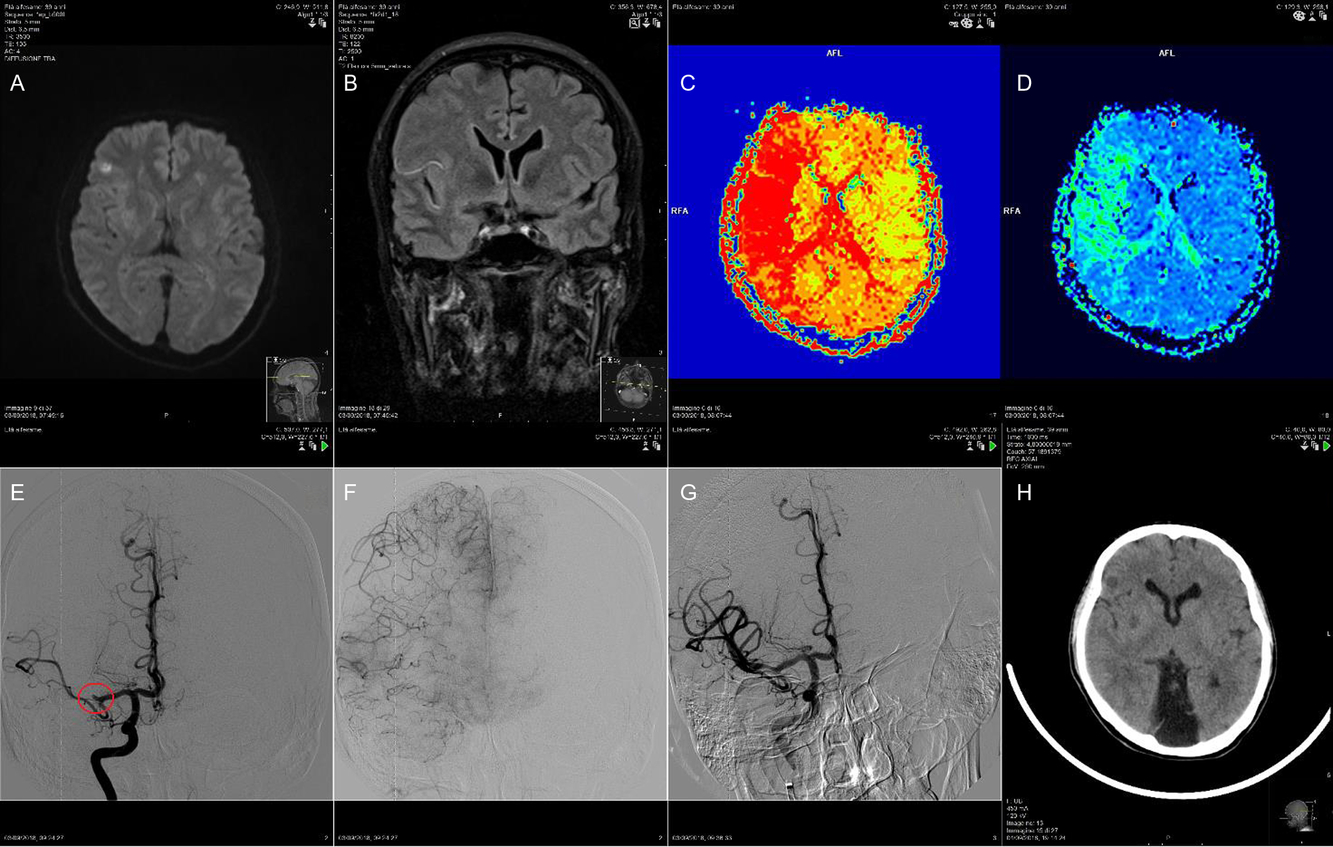

A 39-year-old woman with Eisenmenger’s syndrome, caused by patent ductus arteriosus treated surgically during her childhood, and frequent abnormal vaginal bleedings was admitted to our hospital with dysarthria and left-sided hemiparesis on awakening (NIHSS 5). An episode of uncertain coffee-ground vomitus occurred that morning. Cerebral MRI and angio-MRI were performed, suggesting recent cerebral infarction due to distal M1 segment occlusion of the right middle cerebral artery (MCA); the mismatch was favorable (Figure 1C,D). Right fronto-opercular and lenticular ischemic lesions were detected on diffusion-weighted imaging (DWI) (Figure 1A), with only hyperintense vessel or “Spaghetti sign” – an early sign of acute ischemic stroke – on fluid-attenuated inversion recovery (FLAIR, Figure 1B).

Figure 1: Right fronto-opercular and lenticular ischemic lesions were detected on DWI (A); hyperintense vessel or “Spaghetti sign” on FLAIR (B); MRI perfusion-diffusion (PWI-DWI) showed a favorable mismatch (C and D); cerebral angiography suggested the distal M1 segment occlusion of the right MCA (E); angiographic evaluation of collaterals in the right hemisphere of the brain (F); TICI IIb final angiographic recanalization after the mechanical thrombectomy (G); cerebral CT scan carried out the next day showed only the ischemic lesions already seen on MRI DWI (H).

Intravenous alteplase was not administered because of the episode of coffee-ground vomitus and the history of frequent abnormal vaginal bleedings. Thus, a mechanical thrombectomy using aspiration only was performed, resulting in a thrombolysis in cerebral infarction (TICI) IIb final angiographic recanalization. A cerebral CT scan carried out the next day showed only the ischemic lesions already seen on MRI DWI. The patient recovered completely.